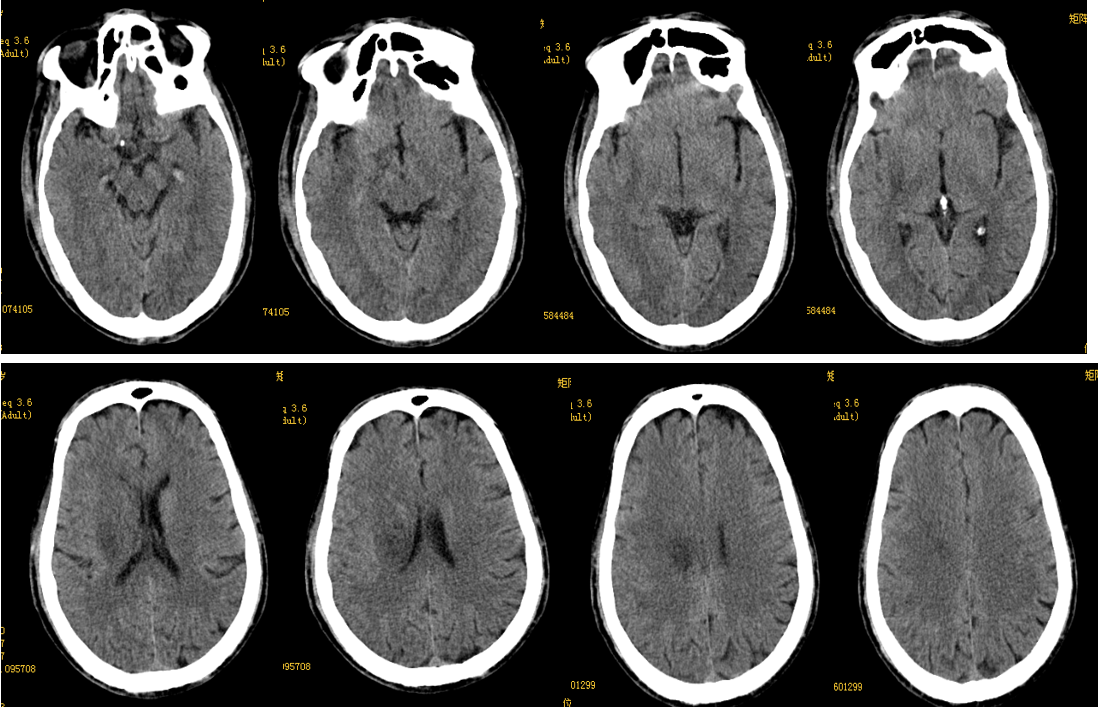

评分:ASPECTS 10分 NIHSS 11分。

出院情况

评分:NIHSS 7分,90天mRS:2分